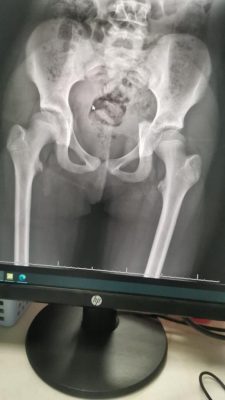

وقالت صحة نجران أن الفريق الطبي بمستشفى نجران العام استقبل الحالة عن طريق الطوارئ وكانت الطفلة تشكو من الآم شديدة مع عدم قدرتها على الحركة التامة وبعد إجراء الفحوسات السريرية والمخبرية والإشعاعية للطفلة اتضح أن لديها كسر في منطقة الحوض .

وقال استشاري جراحة العظام والاصابات واعادة الترميم والمشرف على الحالة انه تقرر على الفور إدخال الطفلة للعمليات لإجراء تدخل جراحي وإعادة ترميم منطقة الحوض التي تعرض لكسور شديدة بسبب إرتطام الطفلة بالأرض ، وتمت العملية بنجاح ونقلها لغرف التنويم لمتابعة الحالة مع المختصين في العلاج الطبيعي وتقديم الخدمات العلاجية والتأهيلية لها لحين استعادة قدرتها على المشي بالتدريج وعودة الحركة بشكلها الطبيعي إنشاء الله .